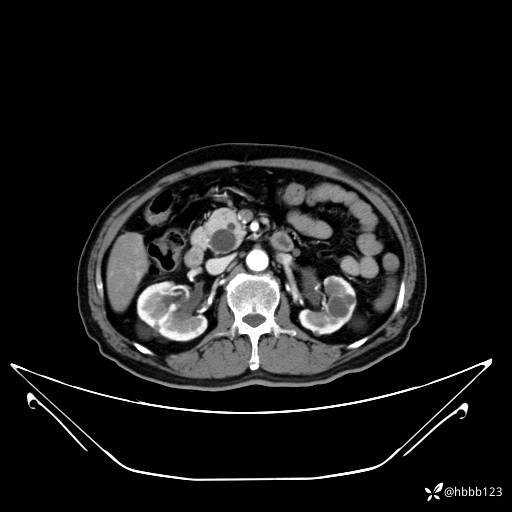

平扫: